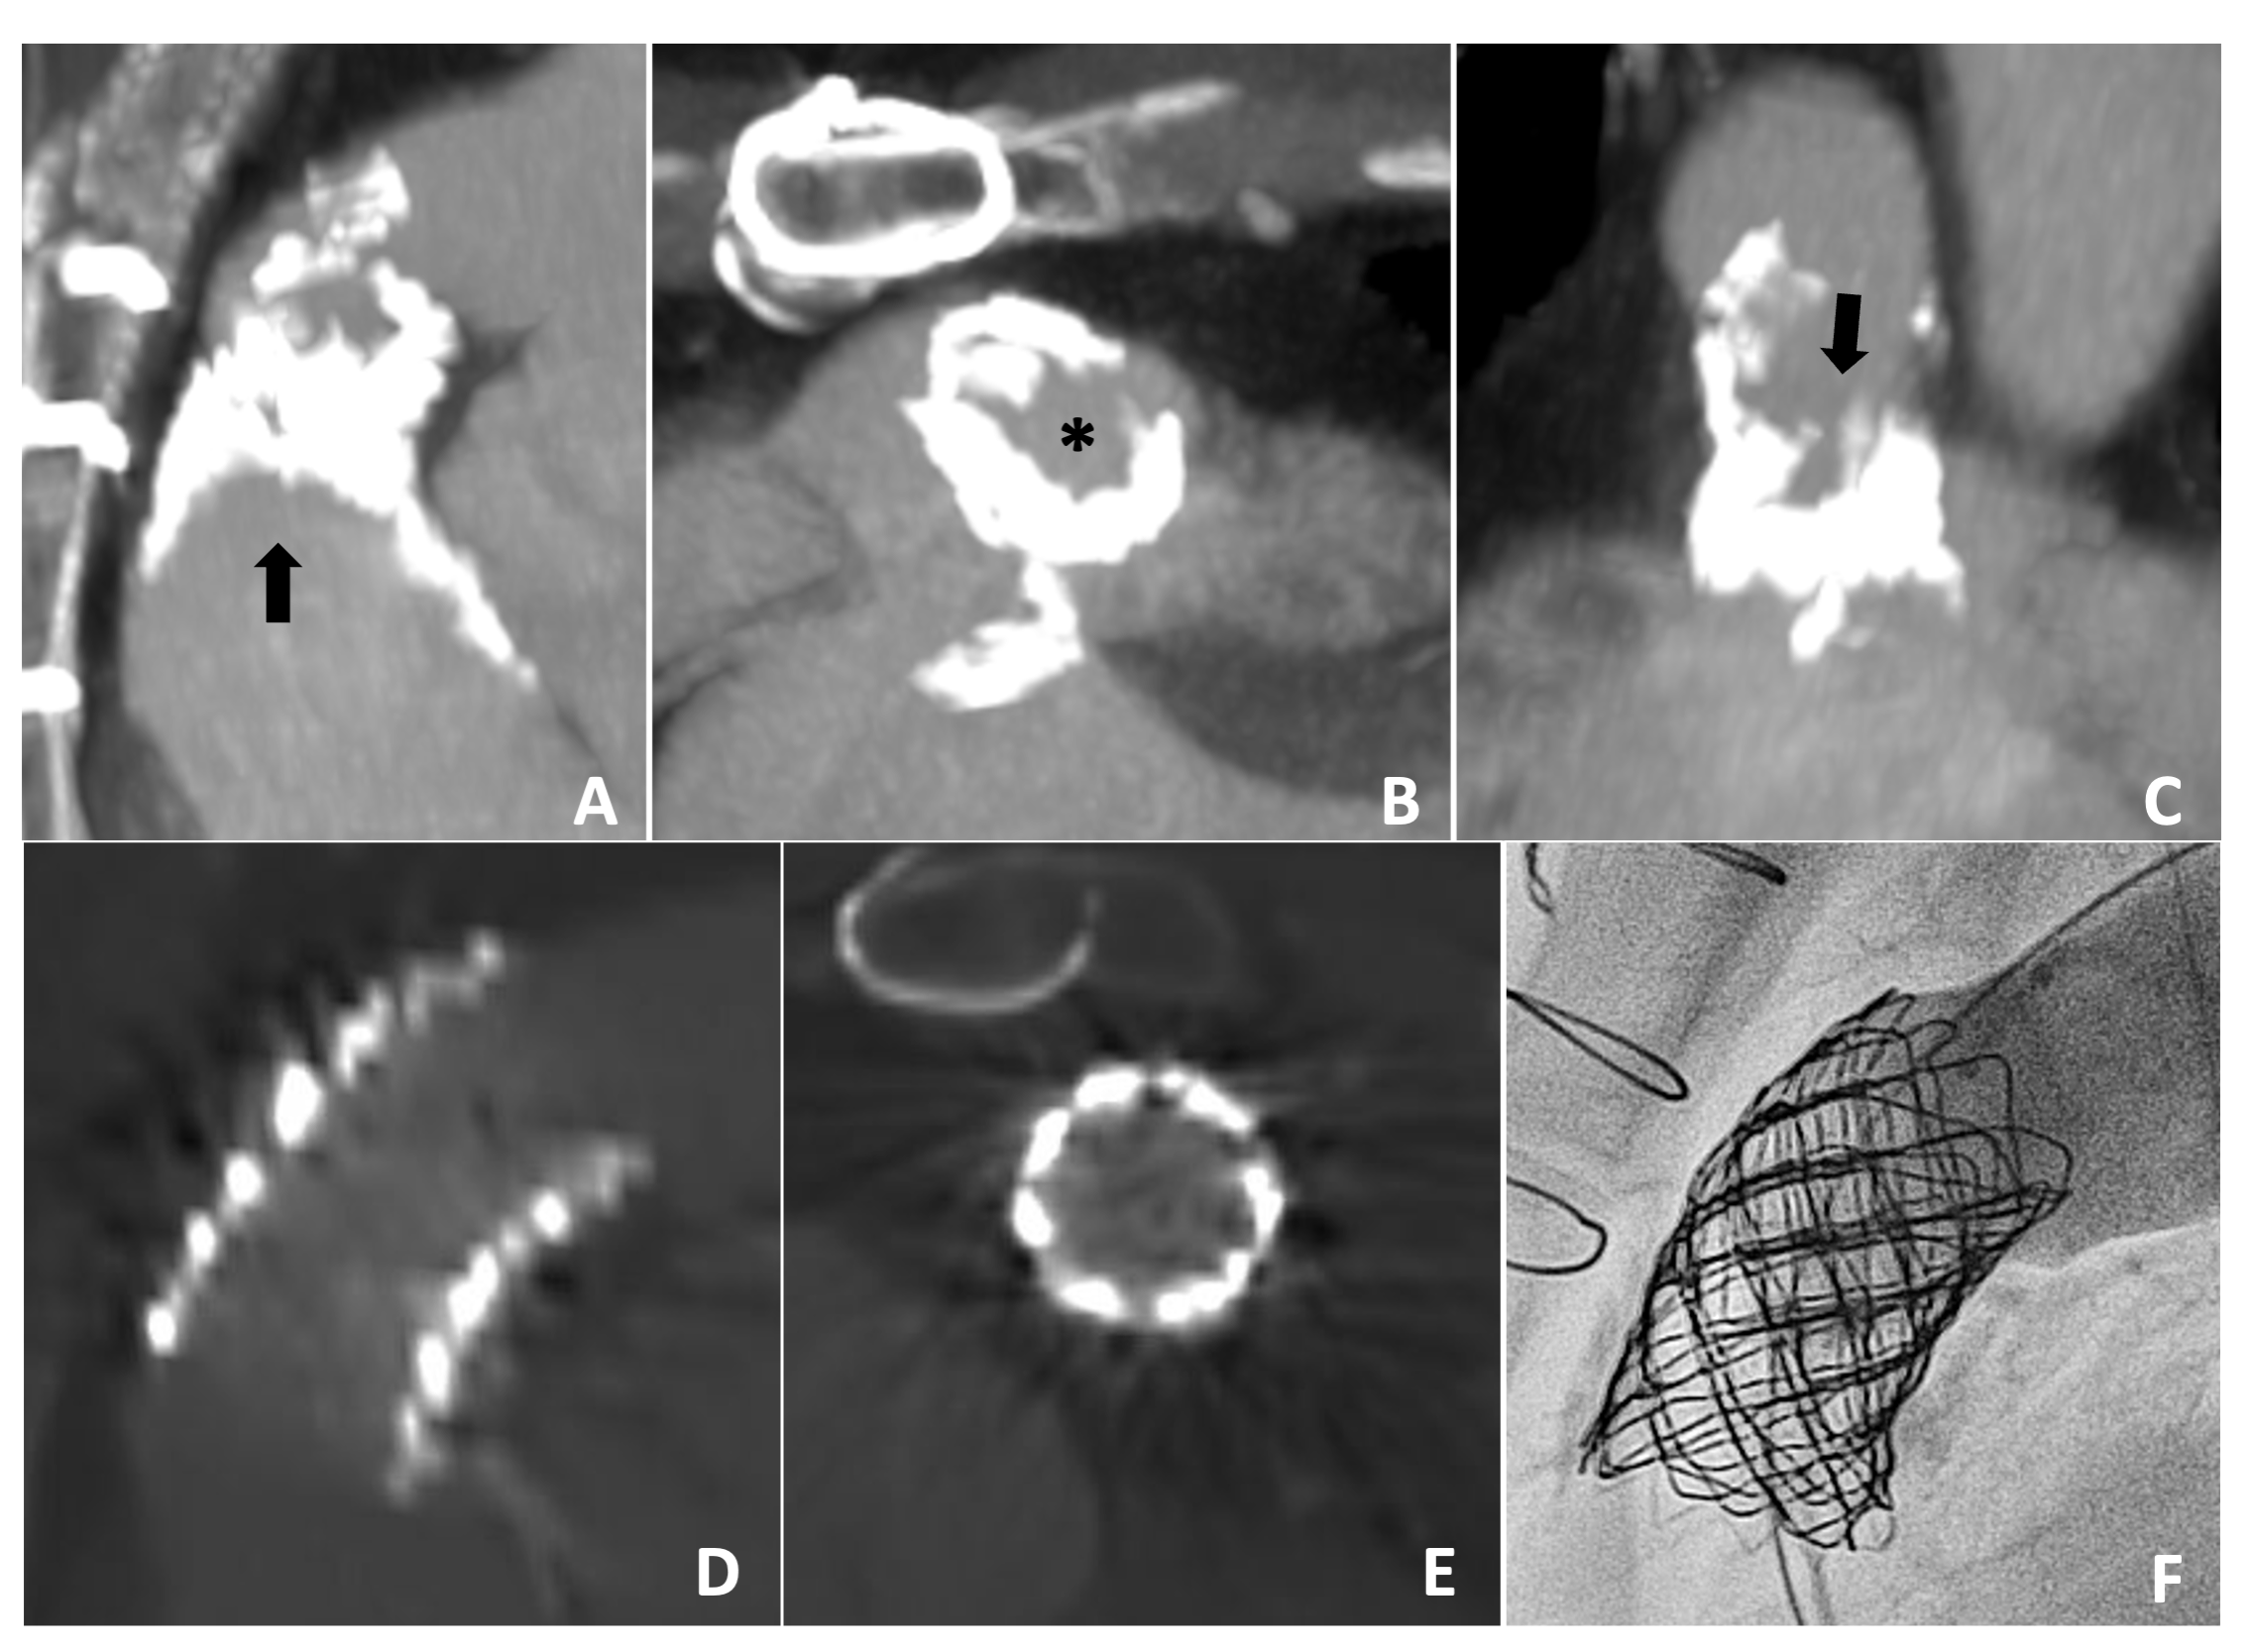

A 38-year-old man with a history of tetralogy of Fallot who underwent staged intracardiac repair of unknown type, which was completed by age 3. He underwent 2 subsequent right ventricle-pulmonary artery (RV-PA) conduit interventions, the last of which was at age 20 with a 23-mm homograft. In the setting of progressive conduit stenosis, with an echocardiography-derived mean gradient of 47 mm Hg, the patient was brought forward for transcatheter conduit rehabilitation. A preprocedural chest CTA revealed heavy circumferential conduit calcifications with a minimum luminal diameter of 8 mm (Figure 3A- C).

Due to concern over conduit fracture with angioplasty alone, and concern related to the efficacy of conduit angioplasty following covered stent placement, the decision was made to proceed with IVL prior to implantation of a covered stent. Coronary angiography demonstrated the coronary arteries to be remote from the conduit. A 12 x 30-mm Shockwave lithotripsy balloon was advanced into the conduit over an 0.018-inch wire and inflated to 4 atm. No balloon waist was appreciated, however, the balloon remained in a stable position with a drop in systemic blood pressure, indicating appropriate apposition to the vessel wall. Thirty lithotripsy pulses were delivered to the calcified homograft, followed by balloon deflation, allowing for systemic blood pressure recovery. This process was repeated 4 times for a total delivery of 150 pulses. A 4.5-cm CCPS was deployed within the conduit over a 22-mm balloon at 6 atm, followed by implantation of a Palmaz XL 4010 within the CCPS. Post-dilation was carried out with a 24-mm Atlas Gold balloon (BD) to 8 atm with full expansion of the stent complex. Follow-up angiography revealed a small, contained distal conduit tear, prompting placement of a second CCPS, which successfully sealed the injury. A Melody valve (Medtronic) was implanted within the stented conduit over a 22-mm Ensemble delivery system (Medtronic) with a reduction in the final conduit gradient from 44 to 4 mm Hg (Figure 3F). The patient experienced a left hemothorax, which was discovered several hours post procedurally, with a CTA showing a fully intact conduit with widely expanded stents (Figure 3D, E) and a bleeding source within the periphery of the left pulmonary vasculature, likely due to a distal wire perforation. The patient was monitored with spontaneous resolution of the bleed within 12 hours and was brought forward for a video-assisted thorascopic surgery 3 days post-procedure for hematoma evacuation.